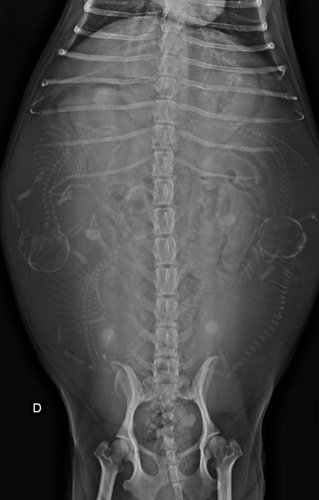

Olá, nossa cachorrinha vai precisar fazer uma cirurgia de cesária de emergência, são 5 filhotes e ela tem 8 anos, já gastamos muito com remédios, veterinários e etc, mais essa cirurgia está fora do nosso alcance agora é pra pouco prazo de pagar, obrigado a todos que conseguirem contribuir!!